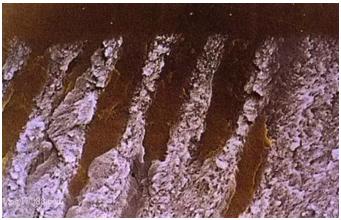

牙本質(zhì)縱斷面。管周牙本質(zhì)被去除,管間牙本質(zhì)膠原纖維暴露(放大倍數(shù)5000)